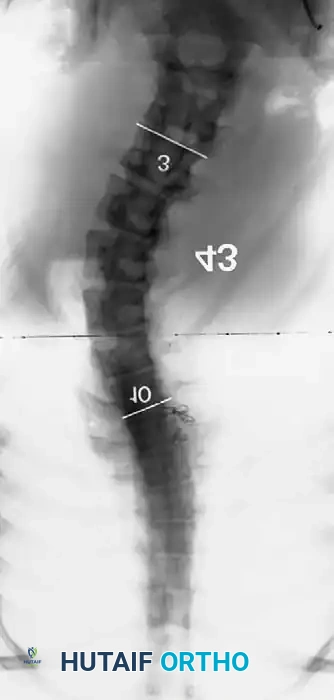

Indications and Curve Selection

The ideal candidate for an anterior approach is a patient with a Lenke Type 4 curve pattern, where the thoracolumbar or lumbar curve is the primary structural component, and the main thoracic or proximal thoracic curves are nonstructural and highly flexible.

Radiographic Prerequisites

Careful preoperative radiographic analysis is mandatory:

1. Flexibility: The thoracolumbar or lumbar curve must demonstrate significant flexibility on side-bending films.

2. Thoracic Curve: The compensatory thoracic curve must be nonstructural, reducing to 25 degrees or less on supine bending films.

3. Fractional Curve: The incomplete (fractional) curve between the lowest instrumented vertebra (LIV) and the sacrum must be carefully evaluated. It must be flexible enough to correct and become horizontal on bending films.

4. Age/Size: The child must be skeletally mature enough to possess vertebral bodies large enough to accommodate anterior screws. Extreme caution is advised when considering anterior systems in children younger than 9 years of age.